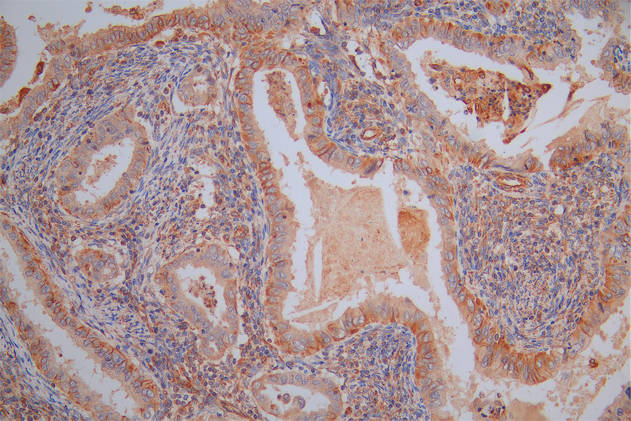

IHC image of CSB-RA215300A0HU diluted at 1:100 and staining in paraffin-embedded human breast cancer performed on a Leica BondTM system. After dewaxing and hydration, antigen retrieval was mediated by high pressure in a citrate buffer (pH 6.0). Section was blocked with 10% normal goat serum 30min at RT. Then primary antibody (1% BSA) was incubated at 4°C overnight. The primary is detected by a Goat anti-rabbit polymer IgG labeled by HRP and visualized using 0.05% DAB.